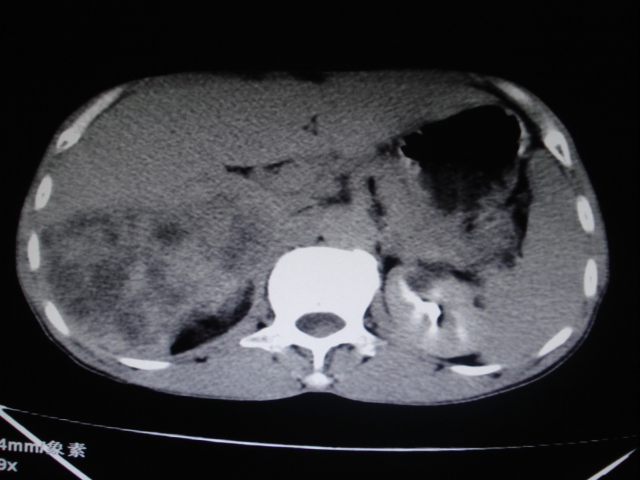

标题: CT24041:肝脏占位,请会诊!

男性,62岁。肝右叶占位,平扫及增强如下,延迟期为15分钟扫描。